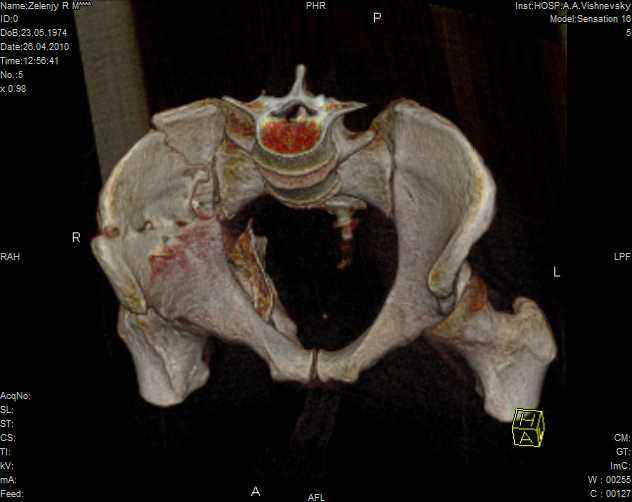

Молодой человек, 35 лет в первых числах января 2010года попал в ДТП, получил перелом правой половины таза.

Был доставлен в одну из ведущих клиник Москвы и прооперирован: была вополнена открытая репозиция и остеосинтез крыла правой подвздошной кости с прилегающей к нему края вертлужной впадины. Но по каким то, мне е понятным соображениям, перелом седалищной кости, проходищая через вертлужную впадину не был отрепонирован ( со слов пациента, доктор сказал что перелом и так срастется).

В настоящее время имеем то что имеем - видно на картинках. Пациент кода то лечился у меня, потому попросил проконсультировать его в создавшейся ситуации.

Мое мнение: пациенту конечно, рано или поздно, предстоит эндопротезирование правого тазобедреного сустава. Но хотелось бы вертлужный компонент поставить в более сформированню вертлужную впадину, чем сейчас имеется.